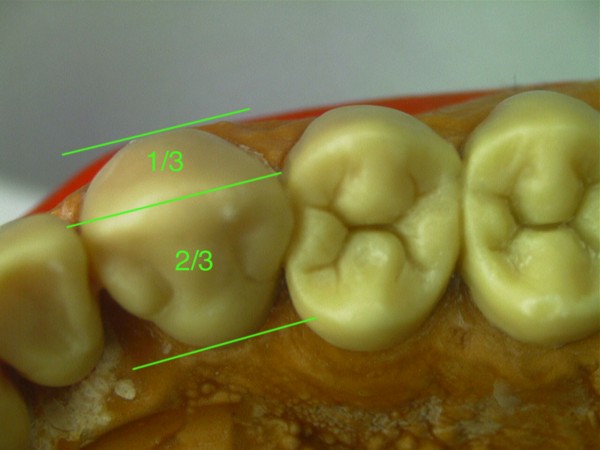

RESUMEN Es un desafío complejo conseguir una secuencia lógica de trabajo en la reconstrucción para una rehabilitación. SUMARY: Trying to acquire a logic working sequence in oral rehabilitation always becomes a defying challenge. The order of the different elements that deal with the whole dental system, as well as its positioning in each one of its planes, turn out into a series of rather difficult details that must be taken into consideration if we really aim towards satisfying results. Alineación Tridimensional- Macrotrípode de la Oclusión- Guía anterior- Microplanos. KEY WORDS: DESARROLLO: Las bases de todo el proceso tienen sus orígenes en una fuente de información tan fidedigna como es el concepto de la ALINEACIÓN TRIDIMENSIONAL La alineación dentaria en relación a unos parámetros regidos por la ATM y la guía anterior constituyen el MACRO TRÍPODE DE LA OCLUSIÓN creando una permanente dependencia de todo el sistema dentario con este; durante el cierre mandibular (la centricidad dentaria) así como durante los movimientos excéntricos (lateralidades y todas sus variantes intermedias). Dependencia que se vera incluso reflejada en detalles tan poco vistosos como son algunos factores elementales de la oclusión: la dirección de surcos. Así pues para sintetizar la totalidad del proceso de una forma breve pero clara destacaremos a continuación los conceptos fundamentales que se tuvieron en cuenta a lo largo de este trabajo. Dado lo extenso del tema nos centraremos fundamentalmente en: A- El desarrollo de La GUIA ANTERIOR, ya que consideramos que da origen al resto del proceso, B- Los VÍNCULOS DIRECTOS entre esta y los sectores posteriores. De la misma manera se muestran casos de estudio de pacientes semejantes al tratado, en que por cuestiones docentes se ha recurrido al encerado de estudio progresivo con ceras de diferente color a fin destacar donde empieza el desarrollo de cúspides, el origen de las crestas internas, así como los rebordes y el alineamiento a que están sujetos cada uno de estos elementos dentro de la individualidad cada pieza. A-GUIA ANTERIOR: Arco Esqueletal, Formas de Empotramiento, Alineamiento. Aunque en ocasiones pueda parecer que se forman situaciones por generación espontánea dada la escasez de información, siempre existen pequeños datos que nos proporcionan claves de referencia para empezar una reconstrucción. La que nos ayuda de una forma destacada y que no necesita de un vínculo directo con los dientes adyacentes, es la relación que se establece entre las piezas 31 y 41 y el movimiento de rotación del conjunto mandibular durante el cierre. Visto desde Sagital, si trazamos una línea entre la base de la emergencia de los centrales y la cabeza de cóndilo del articulador y a continuación proyectamos a 90º una segunda línea, hallamos la equivalencia al eje axial de la pieza (no así la altura). Este detalle nos puede suponer una gran diferencia en casos en los que el capital oclusal esta severamente dañado, allá donde no tenemos referencias anatómicas contiguas a la pieza que reconstruimos( fig 1). A partir de ello podemos empezar a considerar las proporciones en el eje vertical de la pieza ya bien sea a través de información remanente de los cíngulos linguales y de su tamaño en relación al resto del diente, o en ausencia total del capital oclusal (como es el presente caso) en base a las proporciones vestíbulo-linguales proyectadas a lo largo del eje vertical de la pieza. Las proporciones de centrales y caninos inferiores desde un plano horizontal reparten cada una de las caras libres en igual medida desde su borde incisal (50% Vestibular-50% Lingual), de manera que si proyectamos el borde de la primera pieza que hemos construido a partir del arco esqueletal , hacia la superficie que el lateral y canino ocupan en su emergencia (o siguiendo los rebordes/ alveolo en su defecto) podremos situar de una forma precisa el ecuador máximo de cada diente en sus caras libres, alineando así su conjunto (fig. 2). De la misma manera disponemos de unas proporciones entre el ancho V-L de la terminación amelo dentinaria de la pieza y el largo coronario (ej. El largo del canino inferior es aproximadamente eldiámetro V-L + un 30%). Dicha medida la prolongamos por el eje axial de la pieza para obte A partir de éste punto empezamos a pensar en la situación de las piezas superiores. La Dimensión Vertical, Centralizará la Mandíbula y nos aportará la El propio acoplamiento de los caninos de por sí implican una cantidad de desoclusión de las piezas (componente vertical), así como una calidad de desoclusión (componente horizontal del desplazamiento mandibular). Cabe destacar que para asegurar el buen funcionamiento de una guía anterior siempre es más favorable un punto de acoplamiento alto (desde un plano sagital seria una inserción notable del borde incisal inferior contra la vertiente palatina del superior, permitiendo así un importante recorrido en la desoclusión), así como una componente del canino superior muy verticalizada, lo cual impide que el maxilar inferior padezca un movimiento excentrico muy pronunciado, otorgando un patrón de movimientos mucho más verticales con menor distancia recorrida hasta el borde a borde entre caninos (evitaremos caer, eso si, en unos ejes de piezas convergentes -Clases 2/II-, situaciones con un alto grado de contención.) Asi pues prolongamos el eje del canino a partir de su perfil de emergencia. Respetamos las proporciones vestíbulo-linguales en 1/3 a 2/3 (fig. 3-4-5) y lo modelamos en vertical hasta una altura un 25 % mayor que su diámetro V-L a nivel cervical. Ello nos definirá un acople que una vez realizado en ambos caninos tendrá cuantificados unos valores de suma importancia que arrastrarán consigo todo el peso de la centricidad mandibular durante el cierre, así como la dimensión vertical o las propiedades desoclusivas, pues podremos observar como al realizar la lateralidad ya obtenemos espacios de separación uniforme en los cuadrantes posteriores allá donde todavía no hay piezas. Lo mismo hacemos con los centrales: proyectar canal radicular (en el encerado) si lo hay, respetar el ancho de cada una de las caras libres visto siempre desde un plano horizontal a la pieza, y proyectamos en vertical el diámetro cervical + 40-45% para terminar el largo de la pieza. Es importante no confundir la exposición de las caras vestibular y lingual de los dientes observándolos desde un plano horizontal como pieza individual, frente al mismo hecho visto desde su posicionamiento en el modelo, donde las piezas anteriores no se encuentran perpendiculares, sino ligeramente inclinadas hacia vestibular en su borde incisal, con lo cual sus vertientes palatinas se ven más expuestas. En esta fase ya tendremos un acoplamiento a partir del cual visualizar la Protrusiva y los movimientos intermedios compartidos con los caninos durante la función compartida de la guía anterior (fig. 6). Es lógico pensar que cualquier individuo que ha pasado por un proceso tan destructivo como este habrá sufrido movilizaciones a lo largo del tiempo y por lo tanto todas estas aportaciones teóricas son aplicables en la medida en que estemos dispuestos a hacer pequeñas variaciones tan solo milimétricas durante este proceso de alineado. En general cabe hacerse a la idea de que si bien los valores anatómicos / proporciones son prácticamente absolutos, no son igualmente cuantificables los movimientos o alteraciones a que ha sido sujeto un individuo que llega a este nivel de tratamiento (incluidos variaciones en exposición de reborde/alveolo por reabsorción), si bién es cierto que las leyes de proporciones dentarias y alineamiento conjuntamente tratadas pueden llevarnos a recuperar un orden desaparecido en una boca enferma. B-Elementos Intermedios: Escalones Negativos, Áreas de Transición y Microplanos. es mejor alinear el inferior y con ello se podrá acoplar todo el superior sobre él (resulta un tanto más complicado alinear bases de crestas triangulares y rebordes superiores antes que puntas de cúspide inferiores) (fig 7). Esta vendría a ser una referencia inmediata, pero hay que considerar otras. Entre ellas resaltar que según los biotípos se encuentran escalones o saltos negativos en el punto de transición entre anteriores y posteriores. Estos cambios de nivel van directamente asociados al potencial desoclusivo que genera la guía anterior frente al resto de piezas y son elementos funcionales que deben respetarse si se desea preservar la absoluta funcionalidad del conjunto. Este exceso anatómico marca una importante diferencia ya que su inserción en la cara antagónica de los caninos superiores es lo que proporciona la condición a la oclusión de mutuamente protegida. Dependiendo de los biotipos estos escalones pueden ser mayores o menores (fig 8). Al igual que los escalones, van apareciendo según avanzamos hacia los cuadrantes posteriores áreas de transición que suponen una proyección del desarrollo de los cíngulos, con el consecuente aumento del área cortical de las piezas, hasta el desarrollo de cúspides. Detrás de ello encontramos todo un compendio de proporciones que se respetan por igual en todas las denticiones que estudiamos, tanto en lo que respecta al ancho oclusal de cada elemento con las proporciones desde cada una de las caras libres (60% cusp de trabajo-40% cusp de corte) hasta las proporciones de la cara interna o el propio alineamiento de las bases de las crestas internas de las cúspides (fig 9). Normas que como se puede apreciar se han considerado incluso para prever las formas de piezas tan elementales como son las espigas y pernos asi como de la estructura de metal empleados en este caso gracias al encerado La información que aportamos en las fases iniciales siempre se puede alterar y modificar en este proceso de búsqueda de datos. Un proceso en el que sin duda el conocimiento anatómico, los biotipos y sus relaciones entre ejes, así como las relaciones craneométricas que desembocarán en el alineamiento de curvas, nos va a llevar a recopilar infinidad de datos vinculados entre si que permitan de una forma segura, enfocar con precisión un trabajo de estas características. «Tal como se aclara en la segunda entrega, la simbiosis entre clínico y técnico es prioritaria para obtener los logros fundamentales de una OCLUSIÓN ORGÁNICA. Si cuatro son las manos ejecutoras de una rehabilitación como la presentada,debo hacer hincapié en la excelencia de la labor clínica ejecutada por el Dr.Carlos A. Acuña Priano, en la preparación de muñones con alta precisión donde la lectura de los límites fué más que objetiva, como asi la concepción toda de un caso de alta complejidad no solo en el aspecto estructural y médico, sino también en el manejo de una personalidad dificil y controvertida de un paciente extremadamente destruido. El Dr.Carlos A.Acuña Priano,Odontólogo,Master en Implantología y Rehabilitación Oral,de amplia formación en temas de Oclusión, ha enriquecido mi labor de laboratorio como ya lo hiciera nuestro común maestro, el Profesor Anibal Alonso. A ambos, muchas gracias. Pedro Colomina Cursante de estudios de prótesis dental en la escuela Ramon y Cajal de Barcelona (1988)